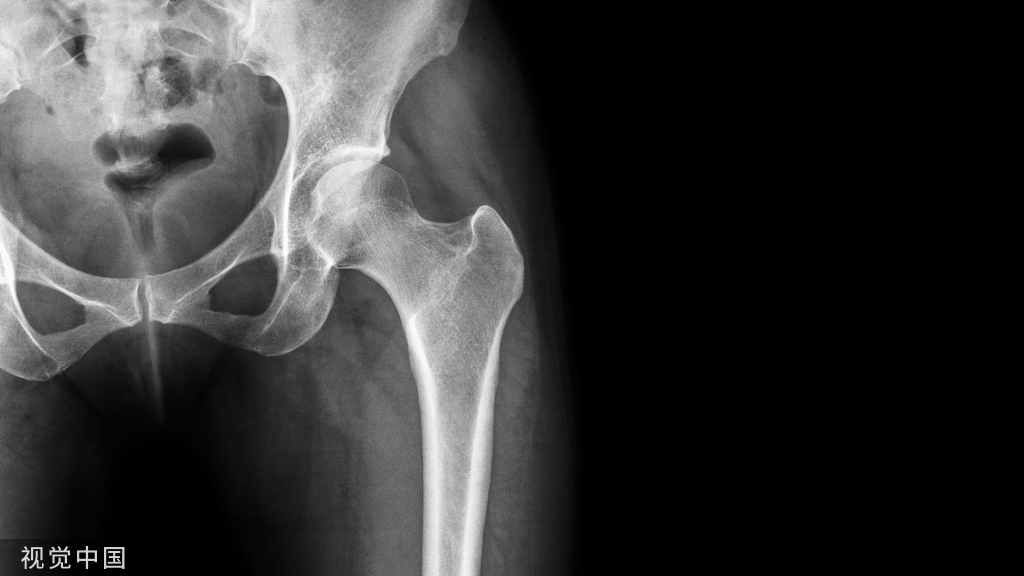

图示:颈椎外伤后C6-7脱位,前纵韧带断裂

图示:C6-7ACDF术后

图示:术后咽后感染并延伸至纵隔